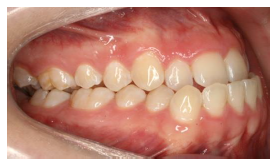

Assinale a alternativa que apresenta o tipo de maloclusão presente abaixo:

A

apinhamento dentário.

B

diastema.

C

protrusão.

D

mordida cruzada.

E

mordida aberta.